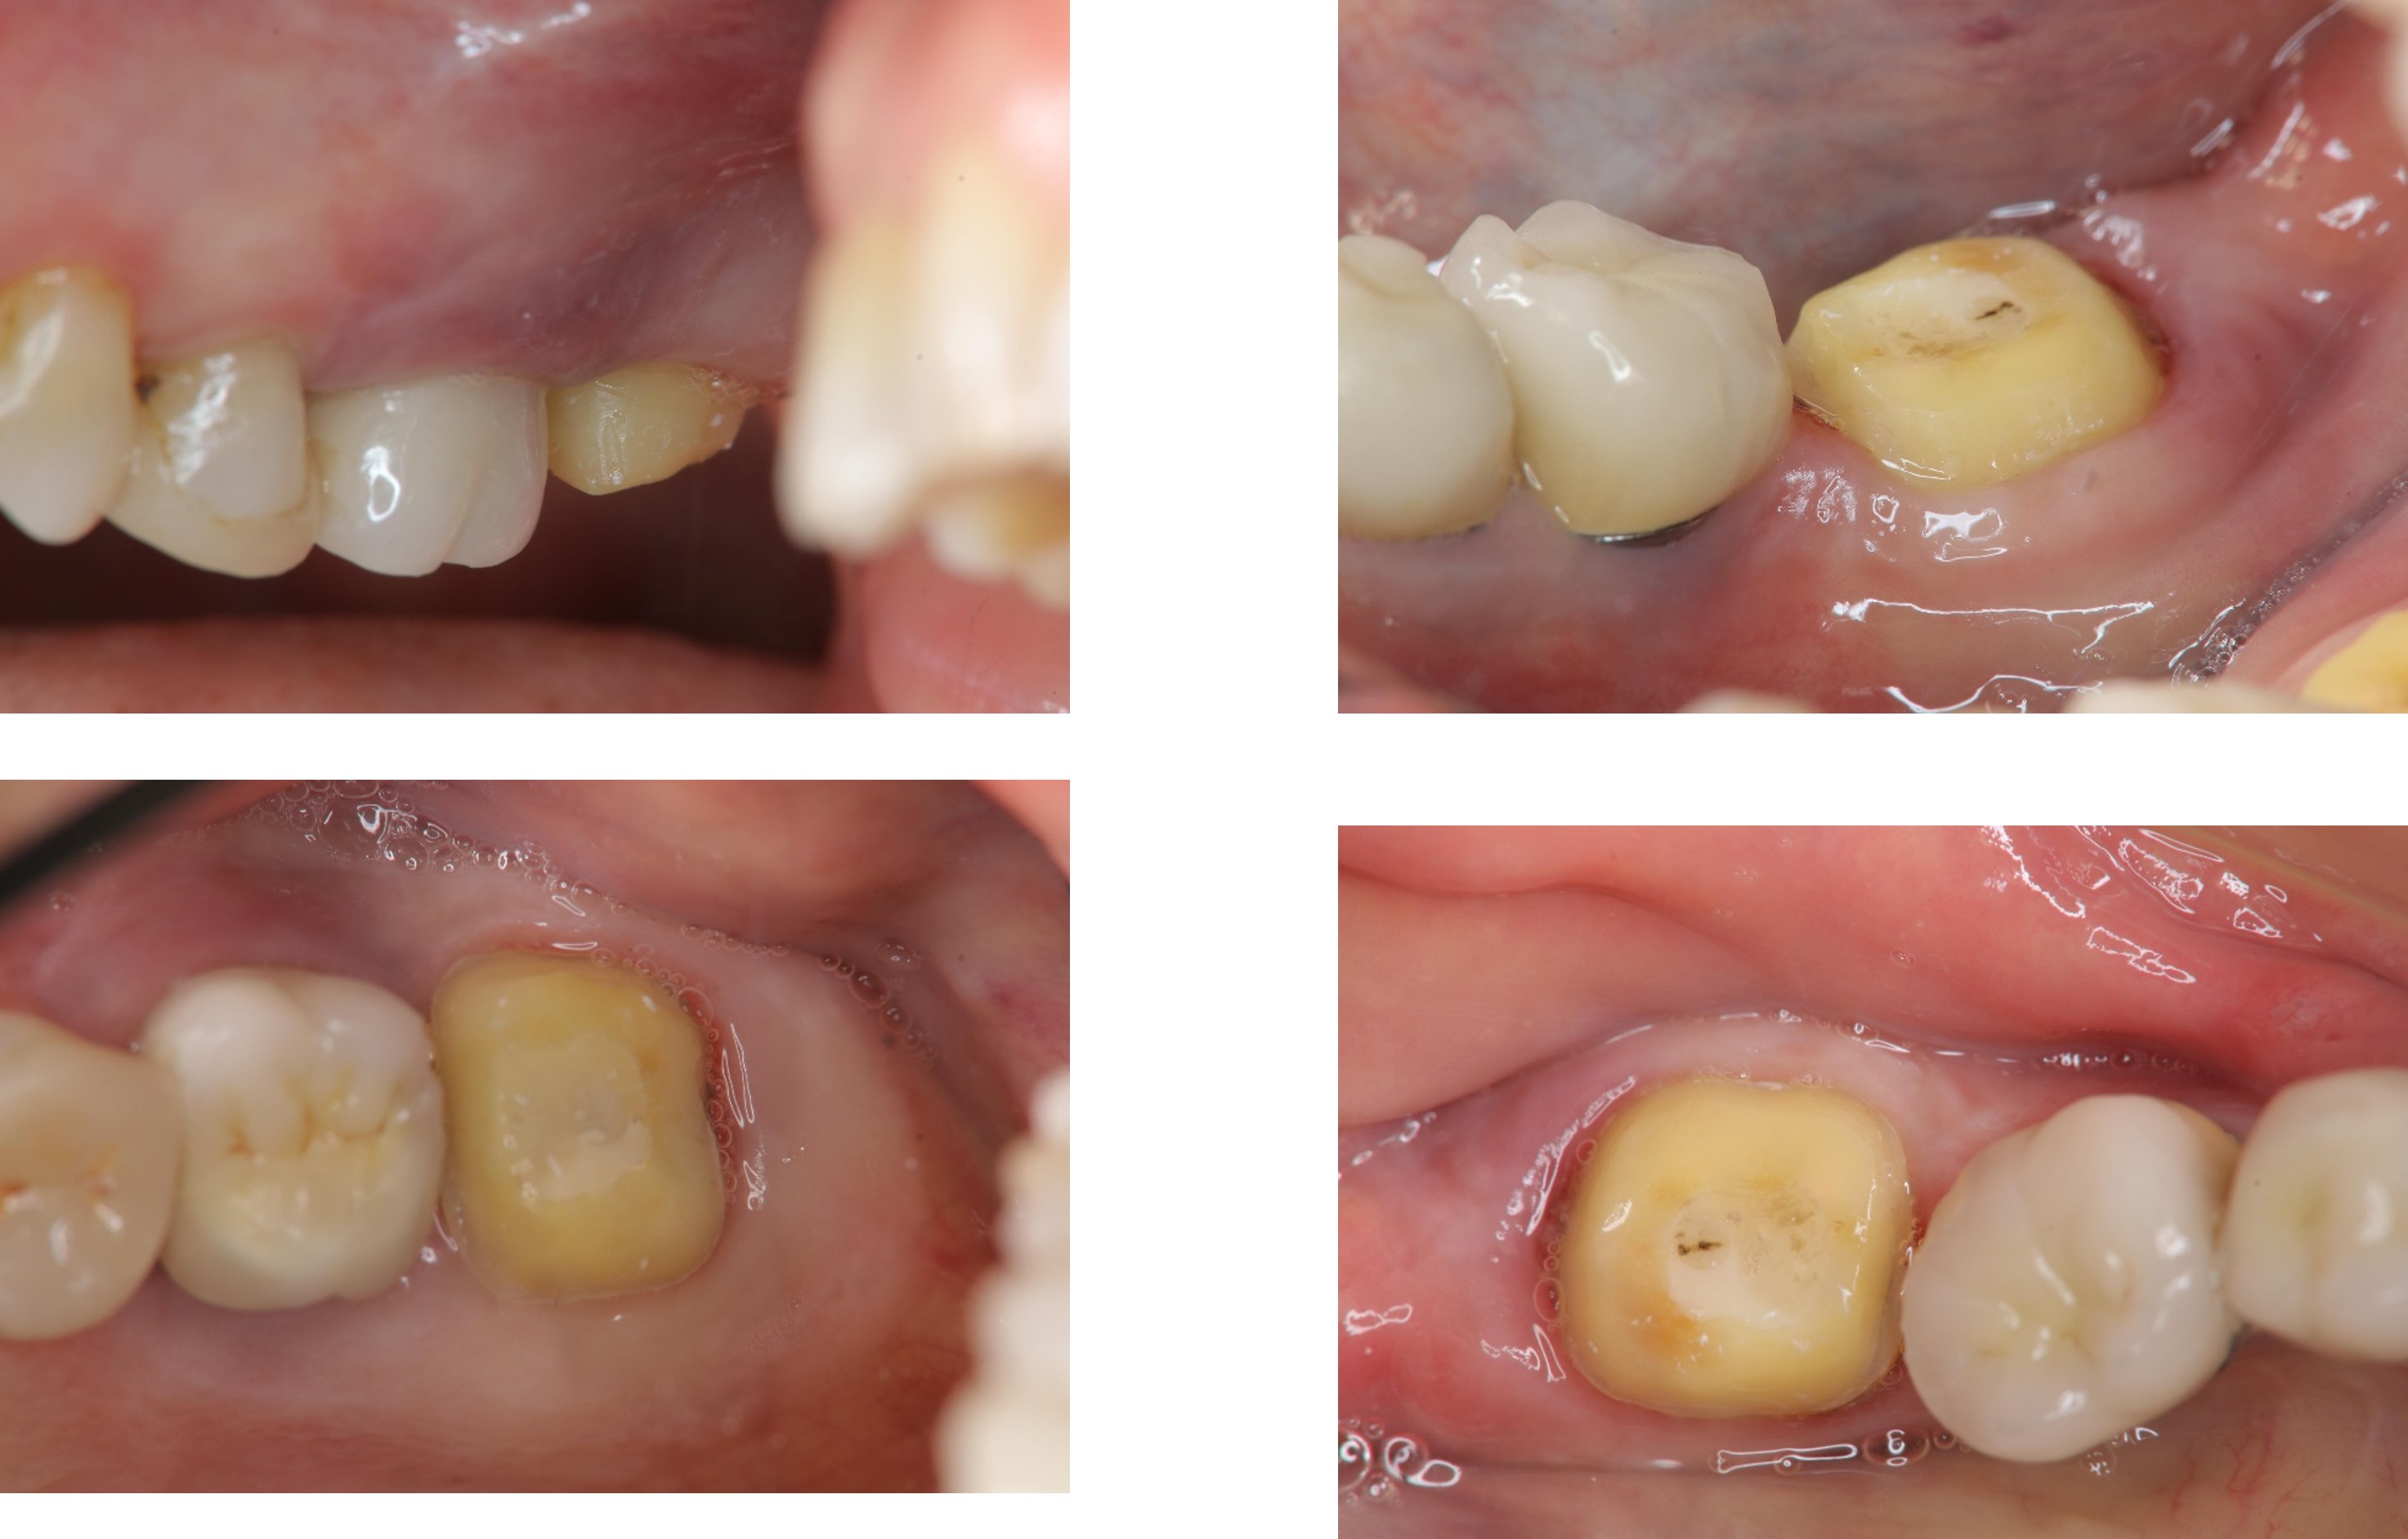

膺復前評估牙齦、牙齒狀態